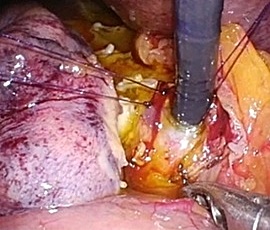

腹腔鏡下胆嚢摘出術の実際

全身麻酔をかけた状態で手術を行います。腹腔鏡下手術では腹部に4カ所の穴、単孔式

腹腔鏡下手術では1カ所の穴を開け、炭酸ガスをおなかの中に入れ、その穴から内視鏡

や手術鉗子を挿入し、画面を見ながら胆嚢を摘出する方法です。

単孔式腹腔鏡下胆嚢摘出術

腹腔鏡手術で胆嚢の摘出と総胆管結石の摘除を同時に行います。胆嚢摘出後、十二指腸

上部総胆管を切開し、胆道鏡を用いて直視下に胆石を除去します。

採石後は胆道鏡で結石遺残のないことを確認します。その後胆管切開部を腹腔鏡下に

体内で結紮縫合を行い、閉鎖します。